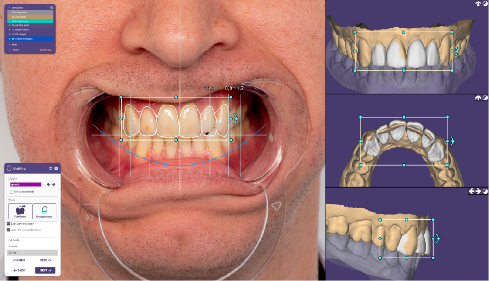

D. Digital Workflow Integration

Contemporary diastema management increasingly incorporates digital technologies:

- Digital Impression Systems

- Intraoral scanning accuracy for anterior teeth: 6-12μm deviation

- Real-time visualization and immediate assessment

- Integration with digital smile design software

- Popular systems: iTero Element 5D, Trios 4, Primescan

2. Digital Smile Design Software

- 2D and 3D smile simulations

- Digital wax-up capabilities

- Precise proportion analysis

- Leading platforms: DSD App, Smile Designer Pro, exocad Smile Creator

- CAD/CAM Integration

- Direct design of restorations

- Milling precision for veneers: ±25μm

- Immediate provisional fabrication capability

- Chairside systems: CEREC Primescan, Planmeca FIT